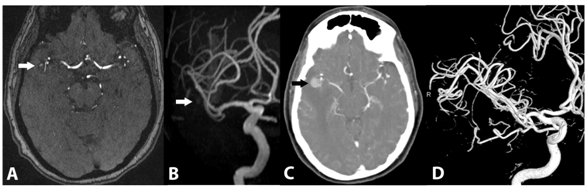

Non-contrast CT scan of the head upon presentation revealed a 10X10X12mm right temporal lobe mass with associated edema. Mass effect was also noted upon the adjacent sulci. The mass effect and edema raised suspicion of a metastatic process. MRI revealed a rounded, enhancing lesion of heterogeneous signal intensity with central areas of bright and low signal on a T1 basis. There was intense magnetic susceptibility artifact on gradient echo T2-weighted sequences, suggesting hemosiderin deposition. There was no evidence of flow-related enhancement or prominent flow voids to suggest an arteriovenous malformation (AVM). Review of MRI performed five months earlier revealed that the lesion was only 5mm in diameter without surrounding edema (Figure 1).

Figure 1 (A) Baseline axial T2 FLAIR MR image demonstrates a 6mm lesion adjacent to the mesial temporal lobe in the Sylvian cistern, immediately adjacent to the MCA bifurcation, with no significant associated edema. (B) Follow up at 5months demonstrates development of vasogenic extending into temporal white matter and temporal stem. (C) Follow up at 6months at a slightly cranial level demonstrates worsening vasogenic edema now extending as far medial as the internal capsule.

MR angiography (MRA) and CT angiography (CTA) was subsequently performed. MRA demonstrated mild T1 shortening without definite flow-related enhancement. CTA revealed a 1cm intensely enhancing focus in the right temporal lobe, at the trifurcation of the right middle cerebral artery. The lesion demonstrated comparable enhancement to the intracranial vasculature. A right M2 branch appeared to course through this lesion, with a faint peripheral blush. There was no evidence of intracranial hemorrhage to indicate rupture (Figure 2). Catheter angiography did not demonstrate a vascular lesion.

Figure 2 Baseline 3D time-of-flight MRA (A) and subvolume MIP MRA (B) images demonstrate mild T1 shortening without definite flow-related enhancement (white arrows). Delayed axial image from a CT angiogram at 5months (C) demonstrates interval increase in size to 6mm with delayed enhancement (black arrow). 3D volumetric reconstructions from a catheter selective right ICA angiogram at 5months (D) demonstrate no evidence of arterial flow to the lesion.